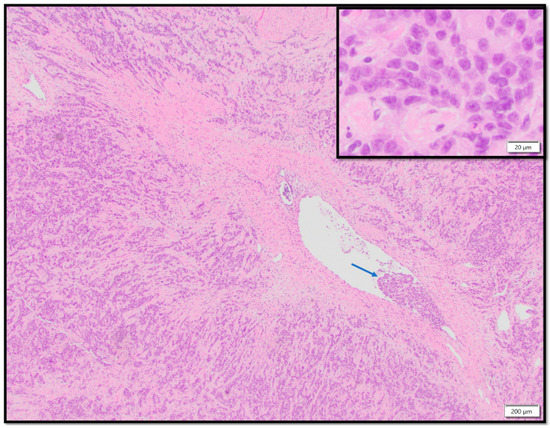

2.3. Pathology